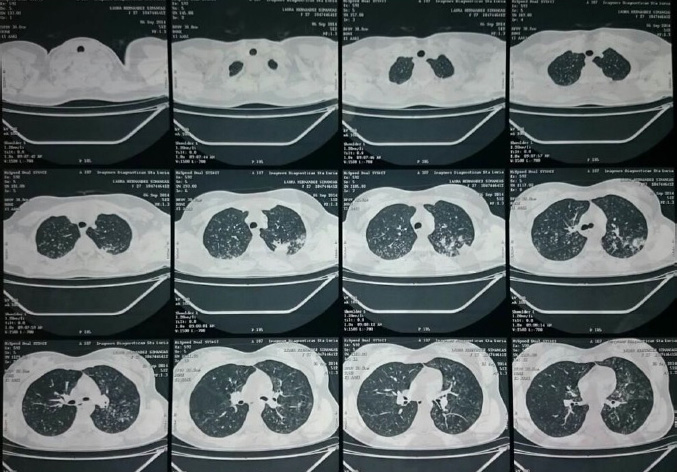

En la tomografía axial computada (TAC) de tórax se observó un engrosamiento y ocupación alveolar con área de cavitación apico posterior del lóbulo superior izquierdo. Se realizó TAC de Tórax de Alta Resolución con hallazgo de nódulos con patrón en árbol de gemación en ambos vértices pulmonares (Fig. 2).

Los estudios de imagen en los pacientes con TB primaria pueden tener una radiografía normal en un 15%, recomendándose realizar estudios como TAC pulmonar. Adicionalmente la TAC de alta resolución, es usada para determinar la enfermedad activa, en donde es posible observar imágenes de estructuras lineales de múltiples ramificaciones de calibre similar procedentes de un único "tallo" (aspecto de "árbol en gemación") se observan con frecuencia en pacientes con amplia difusión broncogénica 13,14.